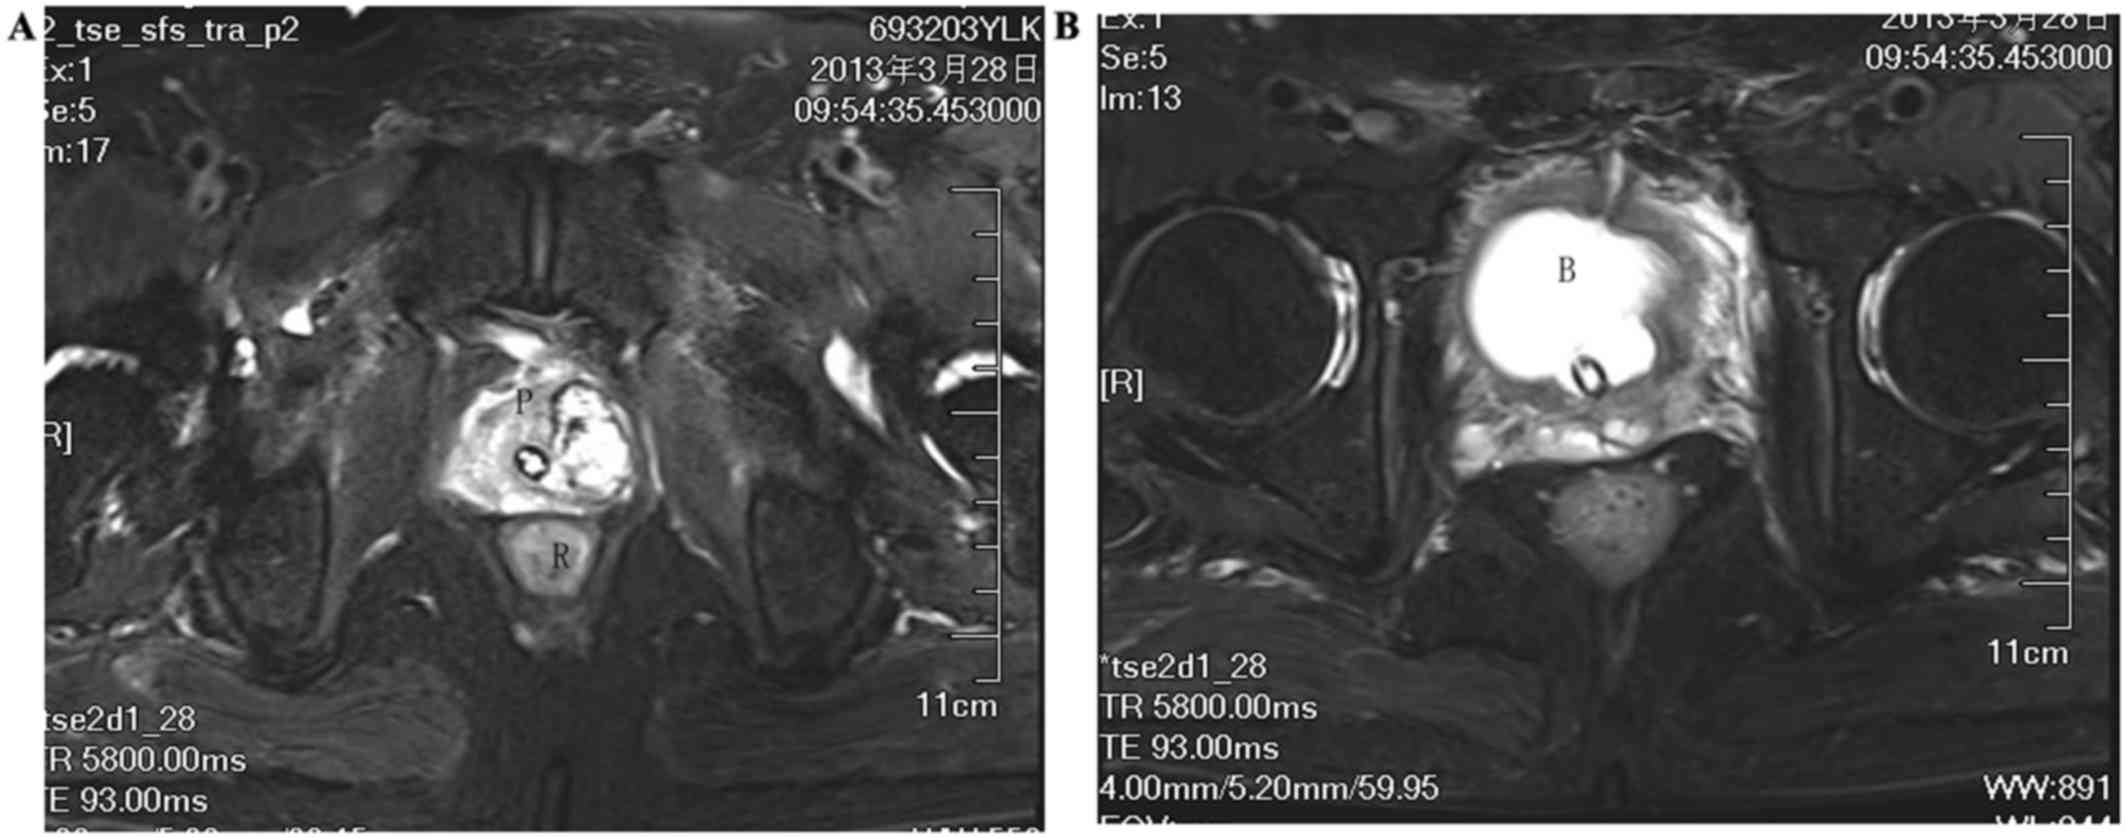

And some men with prostate cancer have more of the protein than others. For prostate cancer that has spread to a small number of areas in other parts of the body. An mri (magnetic resonance imaging) scan uses magnets to create a detailed picture of your prostate and the surrounding tissues. The prostate gland is composed of different types of tissue, divided into zones: According to the paper by patel, et al., It is used to treat early stages of cancer and helps to relieve you from symptoms such as pain. Molecular imaging, a field where a radiotracer is used as the imaging agent, is a useful tool for both detecting and treating prostate cancer. T4 prostate cancer may involve the pelvic floor muscles, the urethral sphincter, the bladder itself, the rectum, or the levator muscles or the pelvic wall. Chade dc, eastham j, graefen m, hu jc, karnes rj, klotz l, et al. Recently, it is suggested that multiparametric mr imaging of the prostate could improve the diagnostic accuracy of the prostate cancer. To help make sense of the options, we spoke with michael zelefsky, vice chair of. Brain metastases from prostate cancer are uncommon and their imaging appearance has not been well defined. Radiation can occur at different times in your treatment plan: